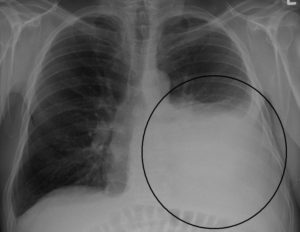

Самым распространенным методом диагностики легких является – флюорография. Но если врач подозревает, что у пациента есть спайки, то больной отправляется на рентген. По рентгеновскому снимку распознать синехию можно по мутным темным пятнам. Она выглядит, как теневое затемнение и неподвижна при вдохе и выдохе.

Плевродиафрагмальная спайка на снимке рентгена

Иногда выявляется деформация грудной клетки и диафрагмы. Чаще всего спаечный процесс отмечается в нижней части легкого. Такой вид спаек – плевродиафрагмальный, а вид спаек в верхней части – плевроапикальный.